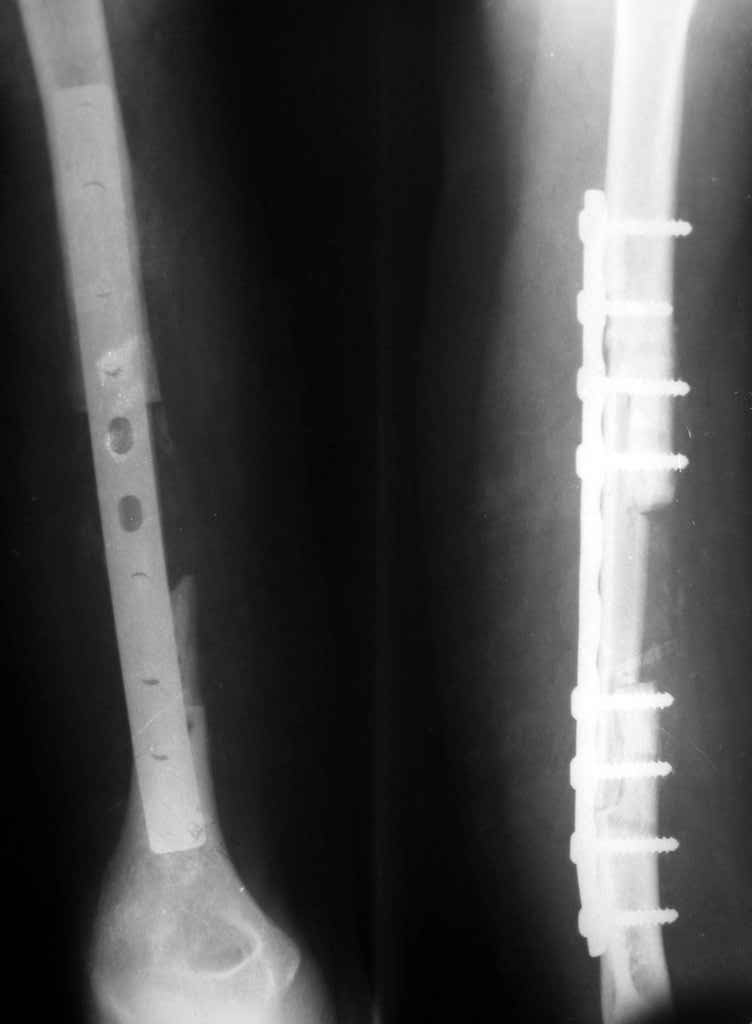

был ли остеосинтез с диастазом - неизвестно, но неадекватность фиксации пластиной достаточно очевидна.

1 пластина тонкая

2 всего 6 шурупов через пластину - для плеча это минимальное требование при свежем переломе

3 проксимальный фрагмент на момент ( или в ходе) второй операции был расколот , о чем свидетельствует наиболее проксимальный lag screw, то есть прокс 3 шурупа через пластину были введены в расколотый фрагмент. Неудивительно, что пластину вырвало

Здравствуйте Владимир! На всех рентгенограммах определяется лизис костной ткани вокруг шурупов, на боковой проекции похоже секвестр, это -- в пользу остеомиелита. Рекомендую: удаление металлоконструкций краевую резекцию концов плечевой кости, ревизию каналов после удаленных шурупов, при наличии признаков остеомиелитических грануляций провести кюретаж. Наложить спице-стержневой АВФ + открытую репозицию отломков. При необходимости проточно- промывное дренирование. Желательно применение Коллапана интраоперационно.